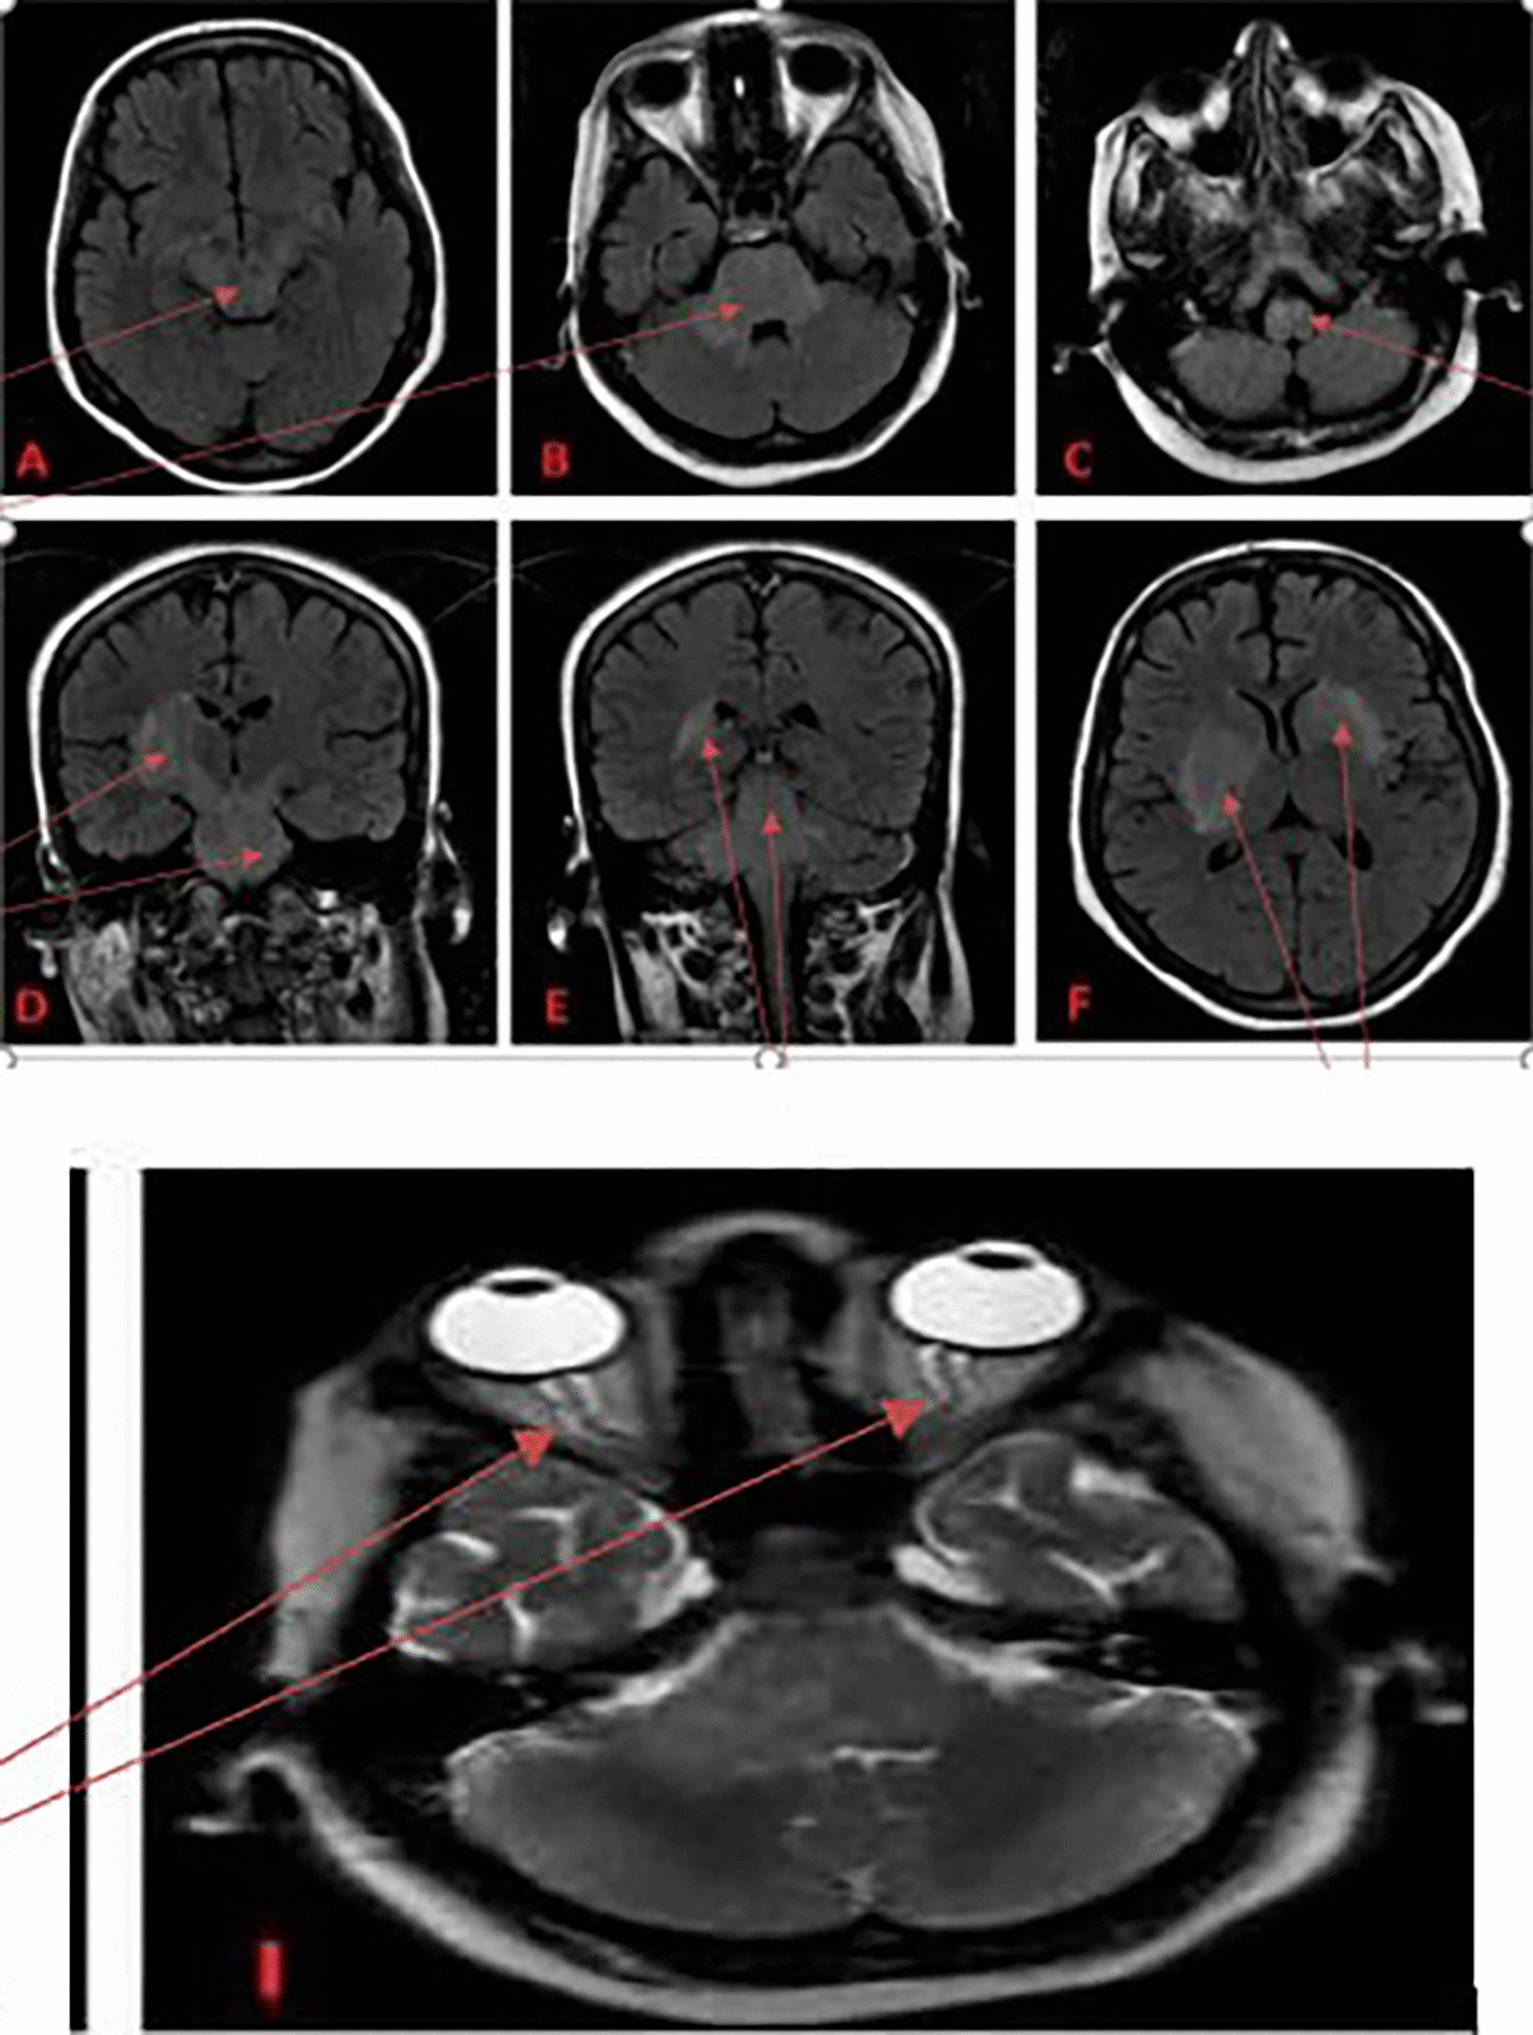

Initial presentation included fever, headache, altered consciousness, and progressive quadriparesis. Cerebrospinal fluid analysis showed lymphocytic predominance and elevated protein, while MRI demonstrated extensive brainstem and deep gray matter hyperintensities on FLAIR and diffusion-weighted imaging, as illustrated in the imaging panels on page 3, involving the midbrain, pons, cerebellar peduncles, basal ganglia, and thalami.

The patient was treated with high-dose corticosteroids and intravenous immunoglobulin (IVIG), resulting in substantial neurological recovery. Follow-up imaging (page 5) demonstrated near-complete resolution of prior lesions, paralleling clinical improvement.